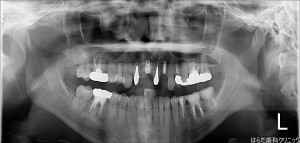

【右上1番、左上2番】インプラント1本埋入、GBR

インプラント埋入とGBRでした。

GBRとは骨再生誘導法になります。

骨を移植して密度を増やし、インプラントを埋入します。